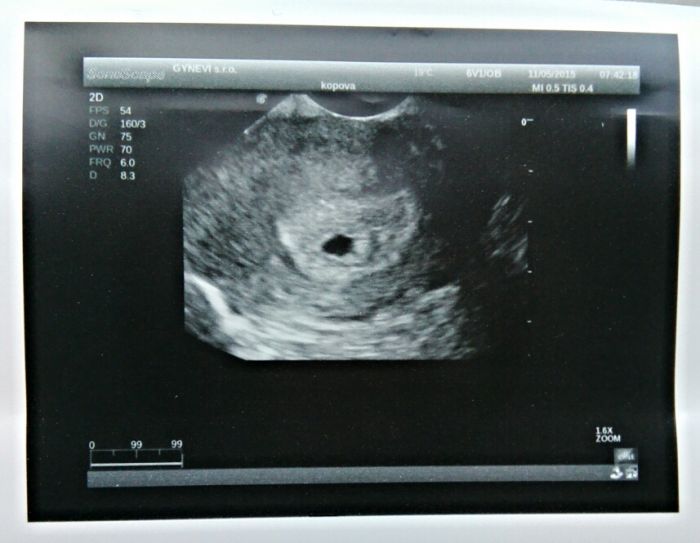

Jinak jsem nasla tady na diskuzich fotku presne toho co bylo na ultrazvuku :)

Hančo,přesně tohle jsem měla na ultrazvuku já.